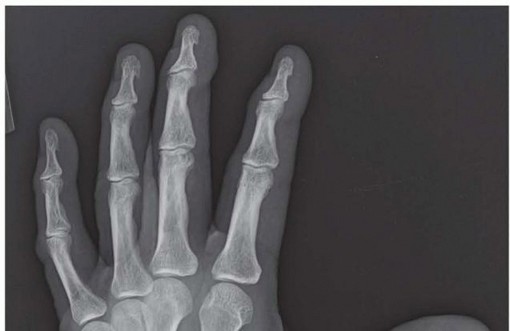

20 MIN READ Proximal Interphalangeal and Metacarpophalangeal Joint Silicone Implant Arthroplasty يناير 2023 Read More

23 MIN READ Proximal Interphalangeal and Metacarpophalangeal Joint Surface Replacement Arthroplasty يناير 2023 Read More